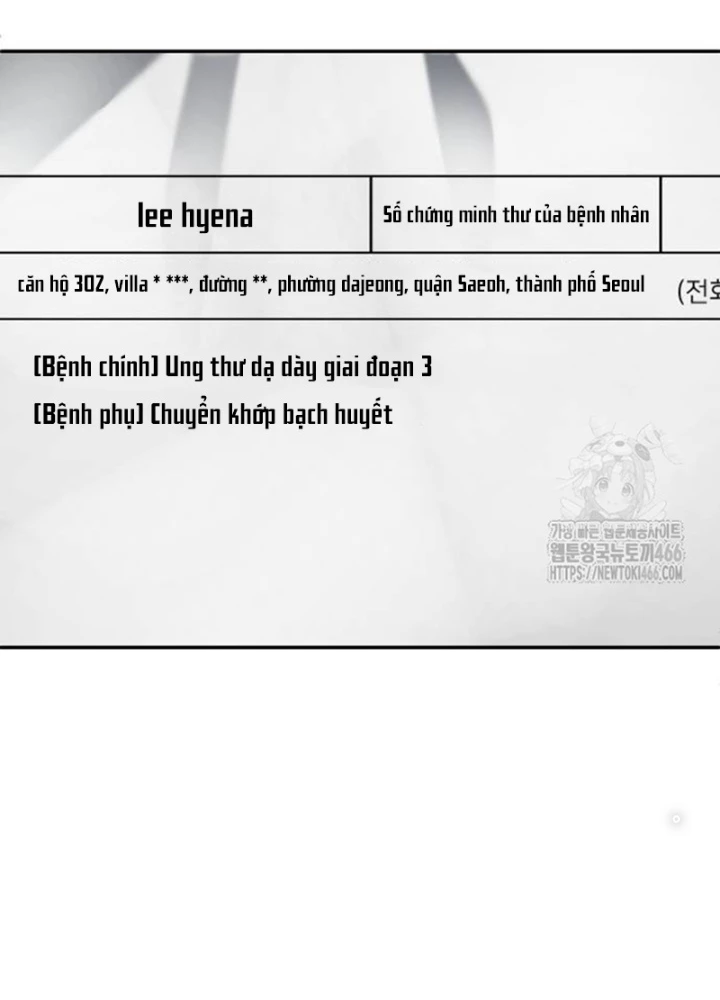

Món Đồ Chơi - Chapter 43